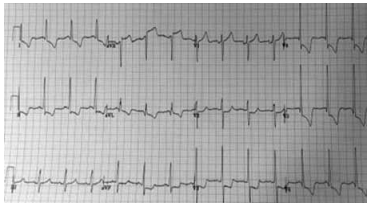

Paciente do sexo masculino, de 58 anos, portador de

diabetes mellitus do tipo 2, dislipidemia e doença arterial

coronariana, é admitido no pronto-socorro com cefaleia

intensa, turvação visual e dispneia súbita há dois horas.

Ao exame físico: PA: 220 × 130 mmHg, FC: 96 bpm,

SpO2: 94% em ar ambiente, crepitações bibasais e B3

audível. A gasometria arterial demostra hipoxemia leve, e

a radiografia de tórax é mostrada a seguir: